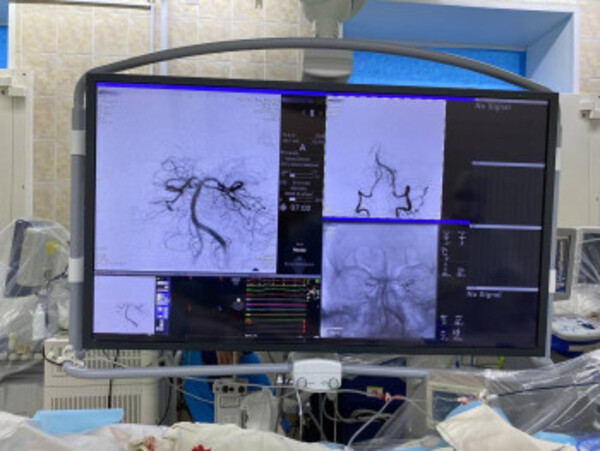

Во время операции. Источник: Минздрав Оренбургской области

После консультации с главным ангионеврологом Минздрава Оренбургской области Александром Чирковым и главным внештатным специалистом по рентген-эндоваскулярным диагностике и лечению Алексеем Деминым пациента доставили в Оренбургскую областную больницу им. В.И. Войнова. Там ему открыли артерию головного мозга в условиях рентген-хирургической операционной.

Из артерии хирурги извлекли большое количество тромбов и восстановили ее проходимость. На следующих день состояние пациента улучшилось.